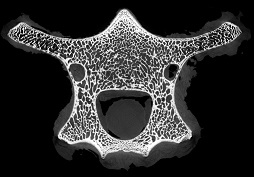

脊椎骨里的“笑臉表情包”

micro CT不僅能夠獲得整體骨量的變化,還能獲得骨骼內(nèi)部骨小梁骨微結(jié)構(gòu)的定量指標(biāo),進(jìn)而將骨小梁微結(jié)構(gòu)指標(biāo)、皮質(zhì)骨指標(biāo)及骨量結(jié)合起來,綜合評(píng)價(jià)骨強(qiáng)度和骨量在骨質(zhì)疏松癥發(fā)生和發(fā)展中的作用。